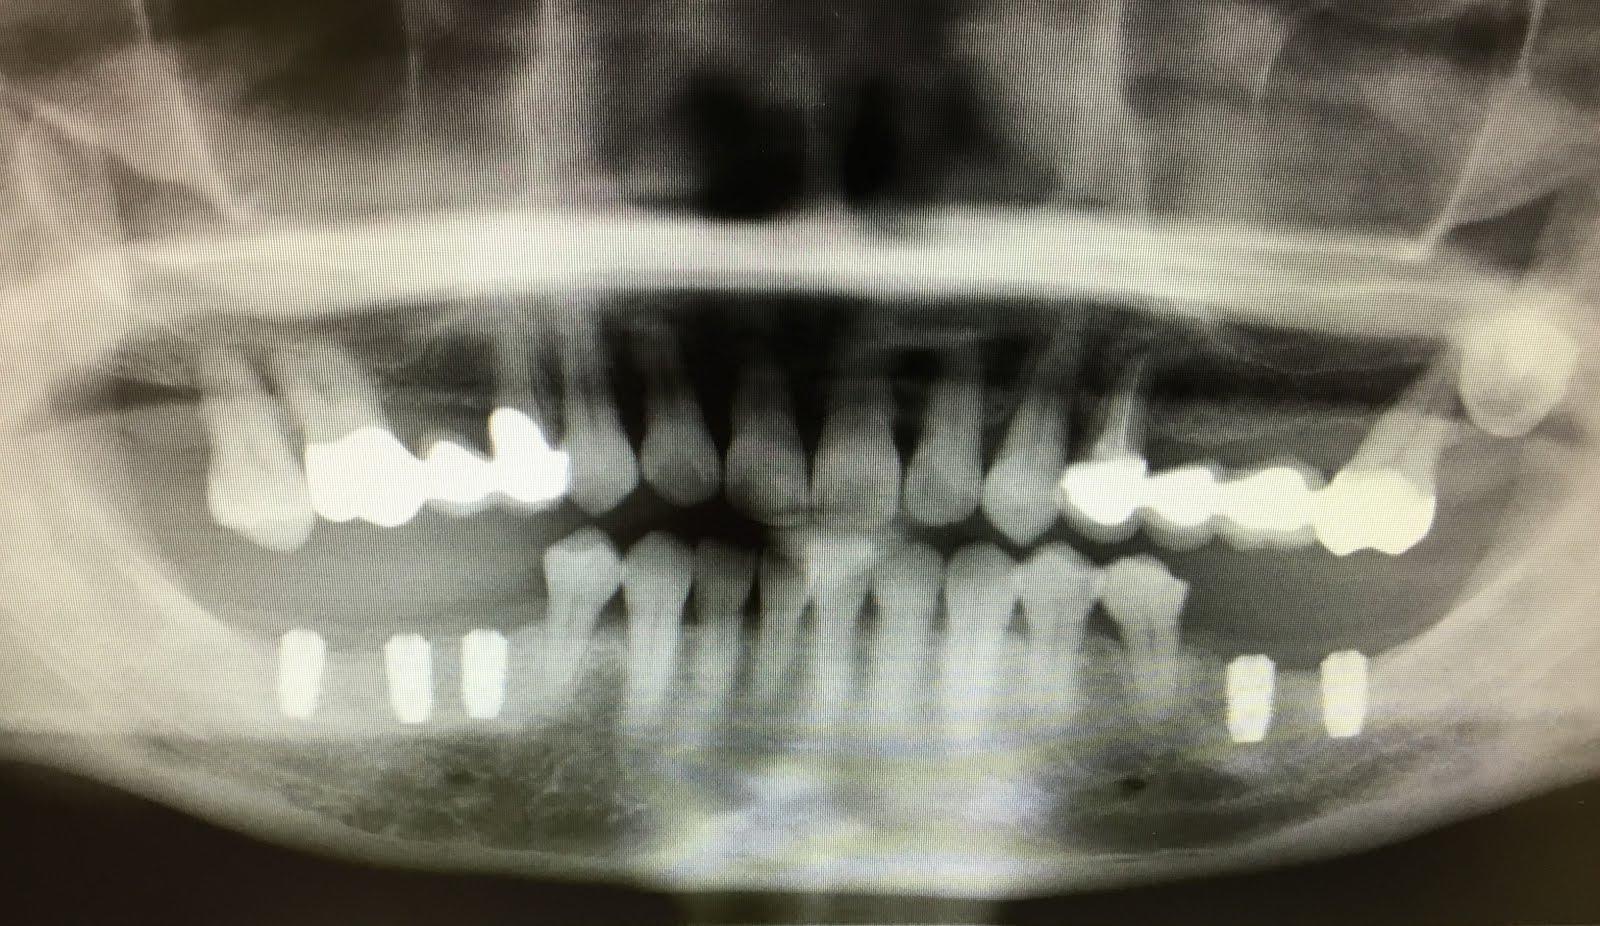

右下3本インプラント埋めた方です。種類はアストラ直径4.0長さ8㎜を3本埋めました。採血したものもいれました。1ヶ月前には左下を2本埋めて最終的には5本白い被せ物を入れる予定です。

術後の経過も良好です。